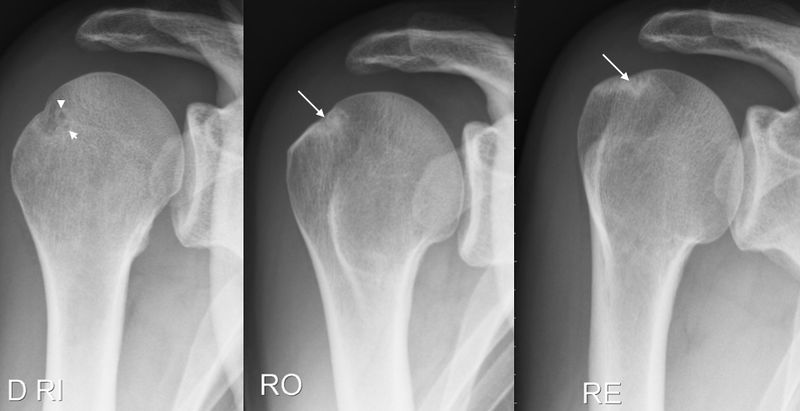

Radiological signs found on X-rays. Images showing bone cysts (short white arrows) or condensation (long white arrows) or on the greater tubercle and glenoid rim, indicating a previous posterosuperior impingement. From Pesquer L, Poussange N, Moreau-Durieux M-H, et al. Le conflit postéro-supérieur de l’épaule. Journal de Radiologie Diagnostique et Interventionnelle 2017;98:296-302, with permission.